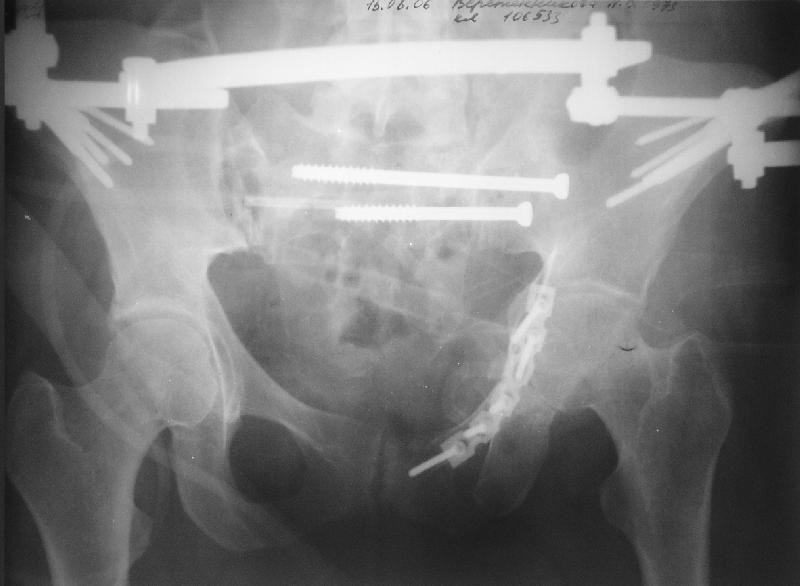

Прооперировали молодую девушку 32 лет спустя 9 мес после травмы. Имелся стойкий болевой синдром, неопороспособность левой н/конечности, моторные и сенсорные нарушения в левой голени и стопе, патологическая подвижность левой половины таза. Первым этапом закрыто в аппарате исправили деформацию ( в течении 2,5 нед). Вторым закрытое введение илиосакральных винтов в крестец (канюллированные 7,2 мм Chm) + туннелизация зоны псевдоартроза спицама Киршнера, реконструкция передних отделов таза, накостный остеосинтез . Аппарат частично демонтирпован, оставлена "передняя рама" После устранения деформации отмечен регресс неврологической симптоматики, уменьшение болевого синдрома. Интересующие вопросы: 1. Прогноз для сращения псевдоартроза крестца. 2. сроки нагрузки весом левой половины таза. Буду очень признателен за ваши мнения по этому поводу.A female 32 y.o. admitted to our unit 9 months after initial injury with pain, inability to bear weight at the left lower limb, sensor and motor disturbances in the left foot and tibia, with mobility of the left hemipelvis.At first closed reduction was performed by an external fixator within 2,5 weeks. After correction her pain decreased and some neurological progress was achieved. Now two iliosacral screws 7,2 mm were inserted, and anterior lesion was fixed by a plate. External fixator was partially unmounted, only anterior frame left in place.Images attached.How would you evaluate chances of healing of the sacrum with the current position?When would you allow weight-bearing of the left leg?THX in advance.